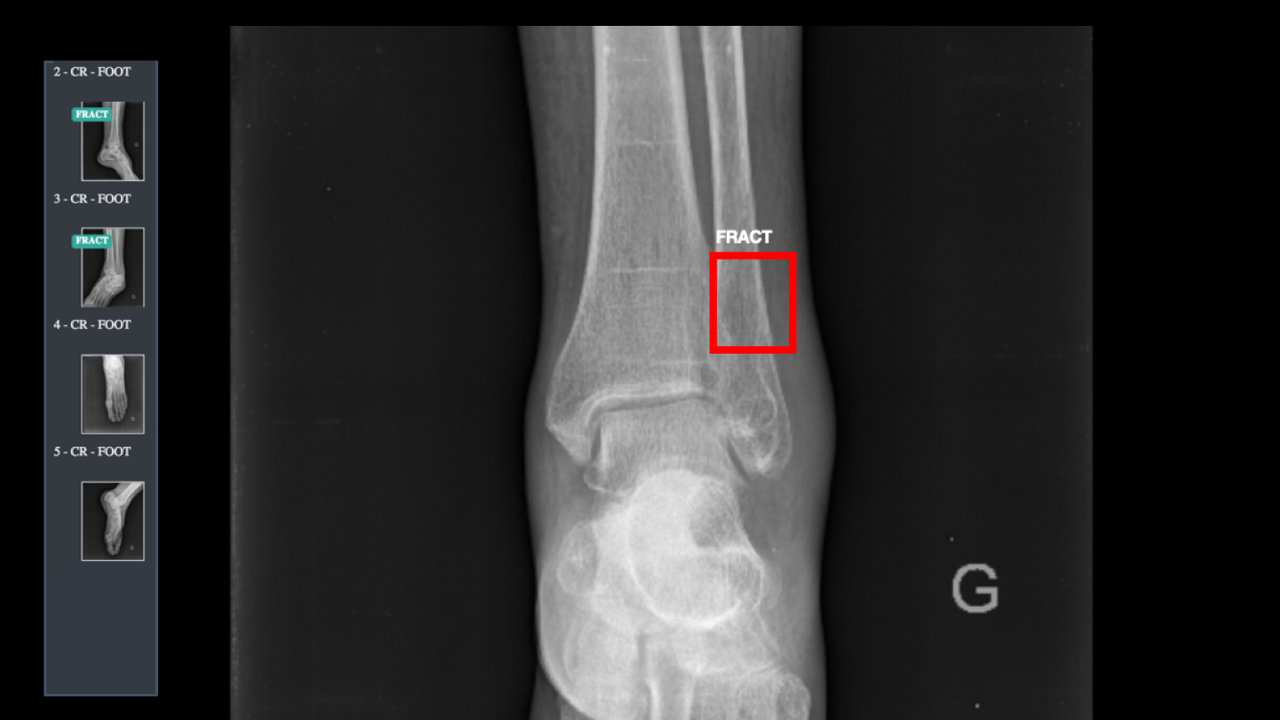

L’augmentation de la charge de travail en imagerie, les interruptions, la fatigue ou encore les biais cognitifs de lecture sont autant de facteurs qui affectent l’interprétation des examens. Les fractures manquées représentent ainsi jusqu’à 80% des erreurs diagnostiques dans les services d’urgence, et sont la 2e cause de plaintes des patients. D’après une étude clinique publiée dans Radiology(1), la solution BoneView de GLEAMER permet de réduire de 30% le taux de faux négatifs, et de gagner en efficacité.

Comme en témoignent les docteurs Romain Malezieux chez Imagerie Loire-Forez à Saint-Etienne et Pascal Kervennic chez RIM 29 Sud à Quimper : « BoneView nous permet de gagner du temps et de gagner en confiance dans nos diagnostics, comme un filet de sécurité face aux erreurs possibles. Le déploiement des solutions GLEAMER se fait 100% à distance. BoneView et ChestView s’intègrent directement au PACS pour renvoyer les résultats dans l’environnement de travail habituel du radiologue. »